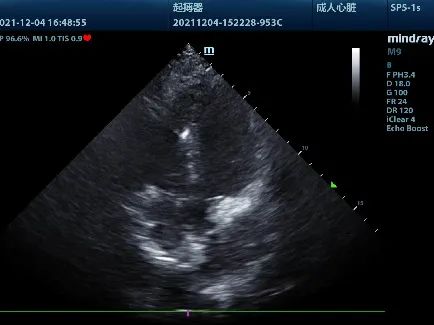

手术在详细周全的计划下进行。严格消毒、铺巾后,郭素峡,陈丽华两位术者顺利进行了左侧腋静脉穿刺,并制作好囊袋。在超声引导下,电极经上腔静脉后顺利进入右心房,跨越三尖瓣,顺利到达右心室。

低位间隔部植入电极导线